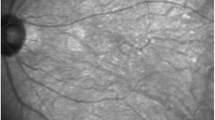

Image grading

Grading for SDD was performed on en face IR and SD-OCT B-scan imaging by two experienced graders (BJH, MMM) based on previously reported criteria (network of roundish irregularities, hyperreflective abnormalities/elevations anterior to the RPE, minimum five lesions) with senior arbitration in cases of doubt (RPF) [6, 19,20,21,22]. Moreover, in case of sufficient image quality, we measured the percentage of area with present SDD on the en face 30° IR image adjusted for individual image size (supplemental figure 1). In addition, we assessed the presence of retinal lesions associated with AMD such as drusen, pigmentary abnormalities, geographic atrophy (GA), and macular neovascularization (MNV) based on SD-OCT.

In participants with data on SDD area, the mean percentage of area affected by SDD was 68% and 66% for the right and left eye, respectively, with large differences between index patients and relatives. Further details and population characteristics can be found in Table 1.